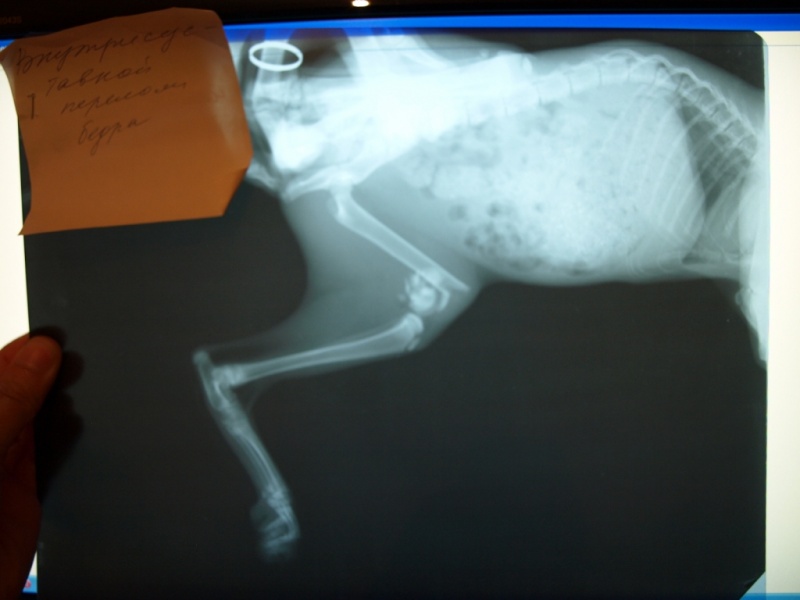

Нужно выложить рентген и лист назначений. По деньгам нужно будет делать отчет.

Проблем, конечно нет, только это время которого нет (( Боюсь, что у нее уже начали кости срастаться.Вам же, наверное, все равно надо будет в клинику идти, договариваться об операции, назначать дату? Это нужно сделать как можно скорее, у врачей тоже свое расписание.

тема о пристроее создана больше месяца назад.Что произошло с котенком я не знаю. Подобрала уже со сломанной лапкойи

Боюсь, что у нее уже начали кости срастатьсяПолучается котёнок месяц с переломом мучался((.